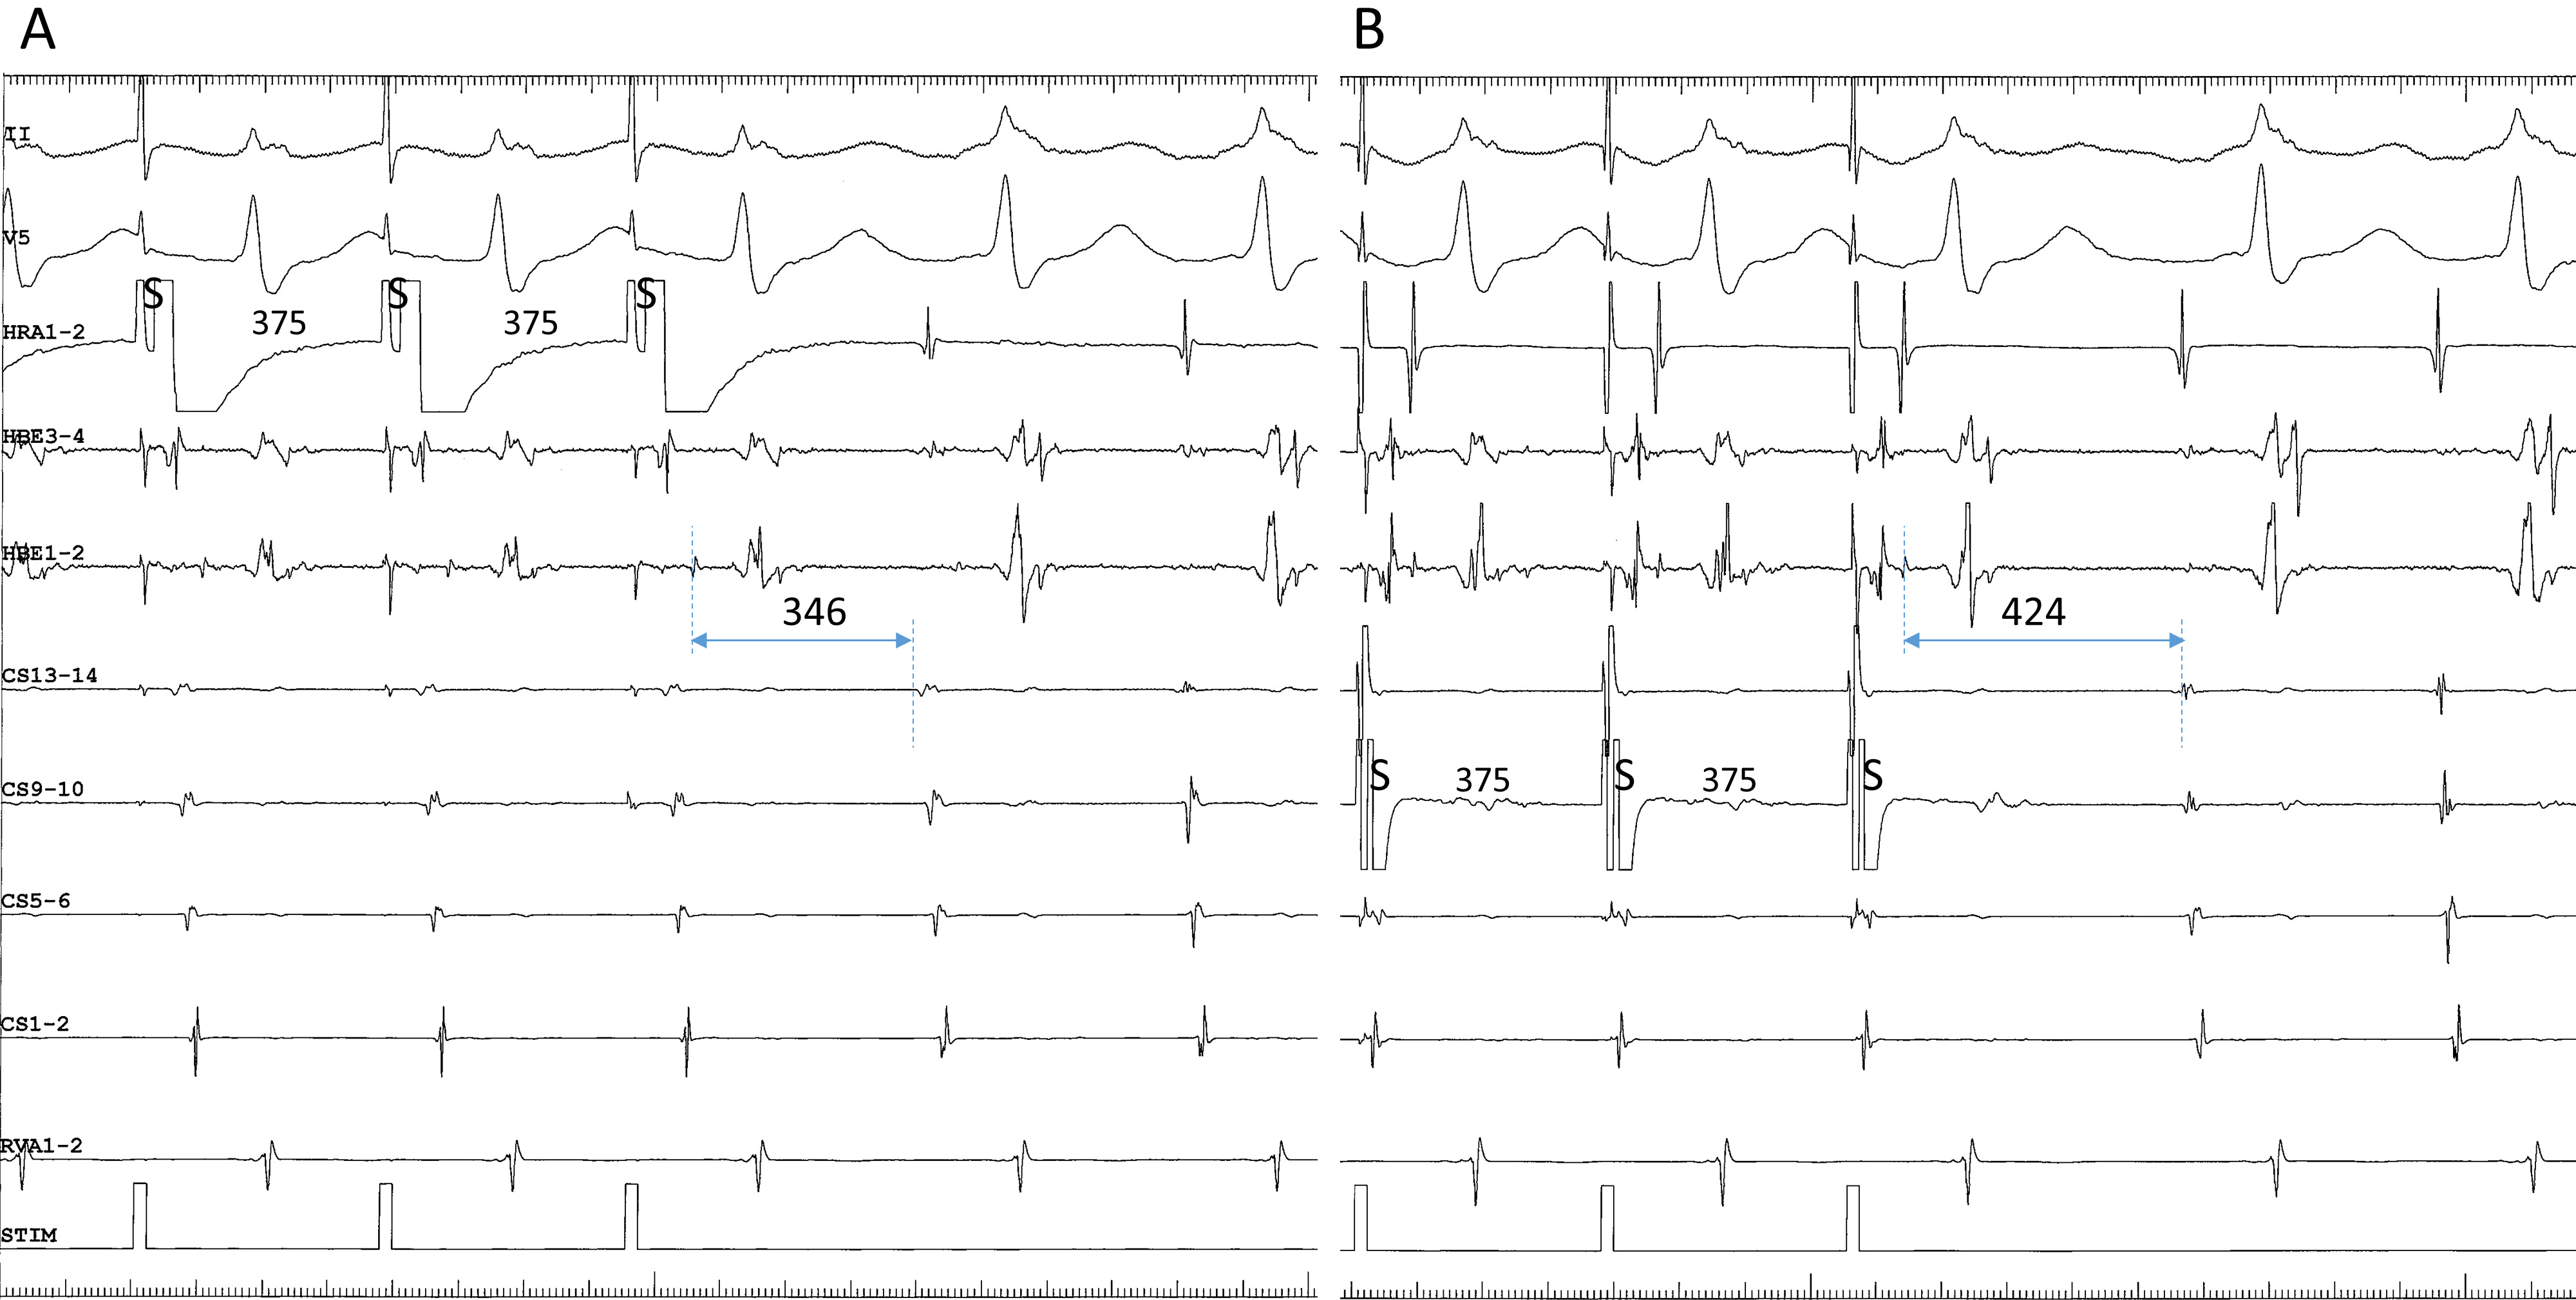

Fourth, ventricular extrastimulation after simultaneous stimulation of atrium and ventricle is useful to induce the superior-type of fast-slow AVNRT by exposing or accelerating a fragile retrograde conduction over the lower common pathway; however, this may cause a complex sequence of AV or VA activation, possibly leading to a misinterpretation of the AV or VA relationship. For example, when the tachycardia follows the last ventricular stimulus (Fig. 3A), it appears to be induced by that stimulus, creating a “pseudo-V-A-V response” (Fig. 3A), when in fact it was induced by atrial stimulation (Fig. 3A). Furthermore, when anterograde conduction of the 1st cycle of the induced tachycardia encounters the refractoriness produced by the last ventricular stimulus in the lower common pathway, the VA relationship upon induction reveals a V-A-A-V response (Fig. 3B) [37].

Fig. 3.(A) pseudo-V-A-V and (B) atypical V-A-A-V responses observed upon initiation of the tachycardia after ventricular extrastimuli (S2) at S1-S2 coupling intervals of 280 (A) and 380 ms (B), following trains of simultaneous atrial and ventricular pacing at an S1-S1 cycle length of 400 ms, in a patient presenting with a superior-type of fast-slow AVNRT. Ventriculoatrial conduction was absent at baseline. In both (A) and (B), the interval between the last atrial S1 and the first atrial electrogram of the tachycardia is similar to the interval between the last atrial S and the first atrial electrogram of the tachycardia induced by regular atrial pacing at an S-S cycle length of 400 ms (C). Therefore, the tachycardia is presumed to be induced by the atrial pacing train and follow the ventricular S2, instead of being induced by the ventricular S2. This resulted in an apparent V-A-V, or pseudo-V-A-V (A), and atypical V-A-A-V responses due to anterograde block in the lower common pathway caused by its refractoriness in the wake of S2 (B). II, surface electrocardiogram lead II; HRA1-2, high right atrium; HBE1-2, His bundle electrogram; CS13-14 to 1-2, proximal to distal coronary sinus; RVA1-2, right ventricular apex.